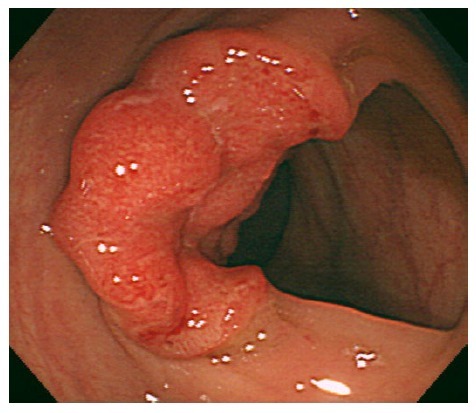

患者男性,64 岁,因大便潜血阳性于当地医院就诊。行结肠镜检查在横结肠发现一典型的肿瘤病灶,直径约 30mm(图 1),标本活检显示中分化管状腺癌。

图 1 第一次结肠镜提示典型的肿瘤病灶,直径 30mm